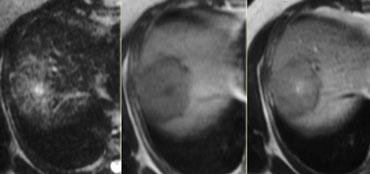

U máu ngấm thuốc nhanh (flash filling) trên thì không tiêm, thì động mạch và thì tĩnh mạch cửa. Lưu ý tỷ trọng tương đương hồ máu.

Các u máu nhỏ có thể biểu hiện ngấm thuốc đồng nhất nhanh chóng (‘flash filling’).

HCC nhỏ và di căn tăng sinh mạch có thể bắt chước u máu nhỏ vì tất cả đều biểu hiện ngấm thuốc đồng nhất trong thì động mạch.

Bằng cách quan sát các thì chụp khác để xem liệu các vùng ngấm thuốc có tương đương hồ máu hay không, thông thường có thể phân biệt được các tổn thương này.